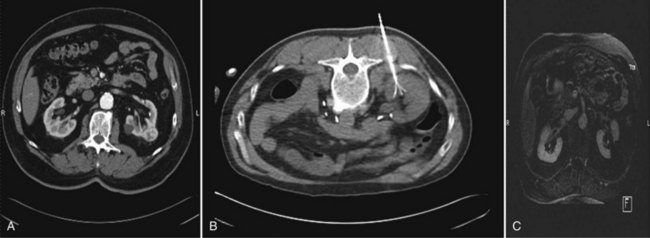

Intravenous contrast (iodinated or gadolinium contrast, depending on the imaging technique chosen and the patient’s renal function) is administered and the lesion identified and characterized. A 20-gauge “finder needle” or access sheath is placed near the expected location of the tumor, and imaging is repeated to confirm localization. It is important to note the depth of the finder needle for subsequent biopsy and probe placement. Using this finder needle as a guide, an 18-gauge Tru-Cut (Cardinal Health, Dublin, OH) core biopsy needle is inserted percutaneously, and positioning is again confirmed with repeat imaging. Specimens are obtained and sent for permanent section. The cryoprobe(s) or RFA probe is/are next inserted in a manner similar to that of the core biopsy needle. Cryoprobe positioning and positioning of the RFA probe, and prongs are again confirmed with repeat imaging. Treatment is carried out in a fashion similar to that described for laparoscopic cryoablation/radiofrequency ablation (Fig. 56-2). Again, a “track burn” can be performed with percutaneous RFA. With percutaneous cryoablation, the cryoprobe is removed and repeat imaging performed to evaluate for potential bleeding. With either technique, a postablation contrasted imaging study is performed to determine the adequacy of treatment.